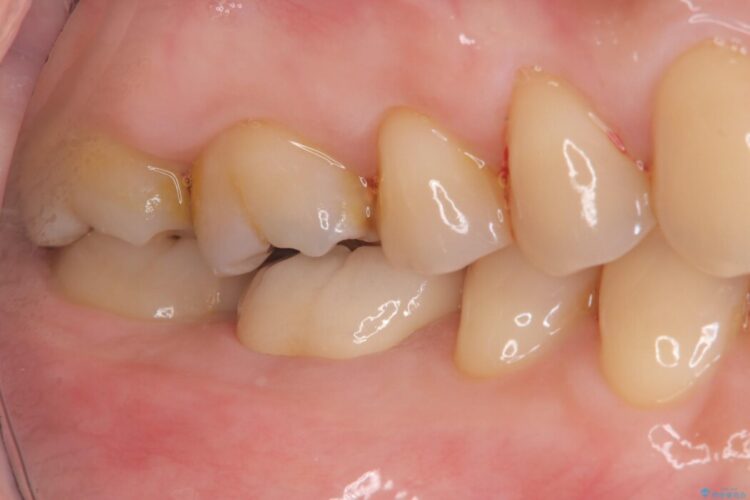

右下奥歯(6番)の激しい痛みと、歯ぐきの腫れを主訴にご来院されました。

術後の経過は非常に良く、あんなに大きかった膿の袋は消え、健康な骨が再生しているのが確認できました。痛みや腫れも消えて抜歯を免れ、現在は被せ物を入れてしっかりお食事を楽しんでいただけるようになっています。